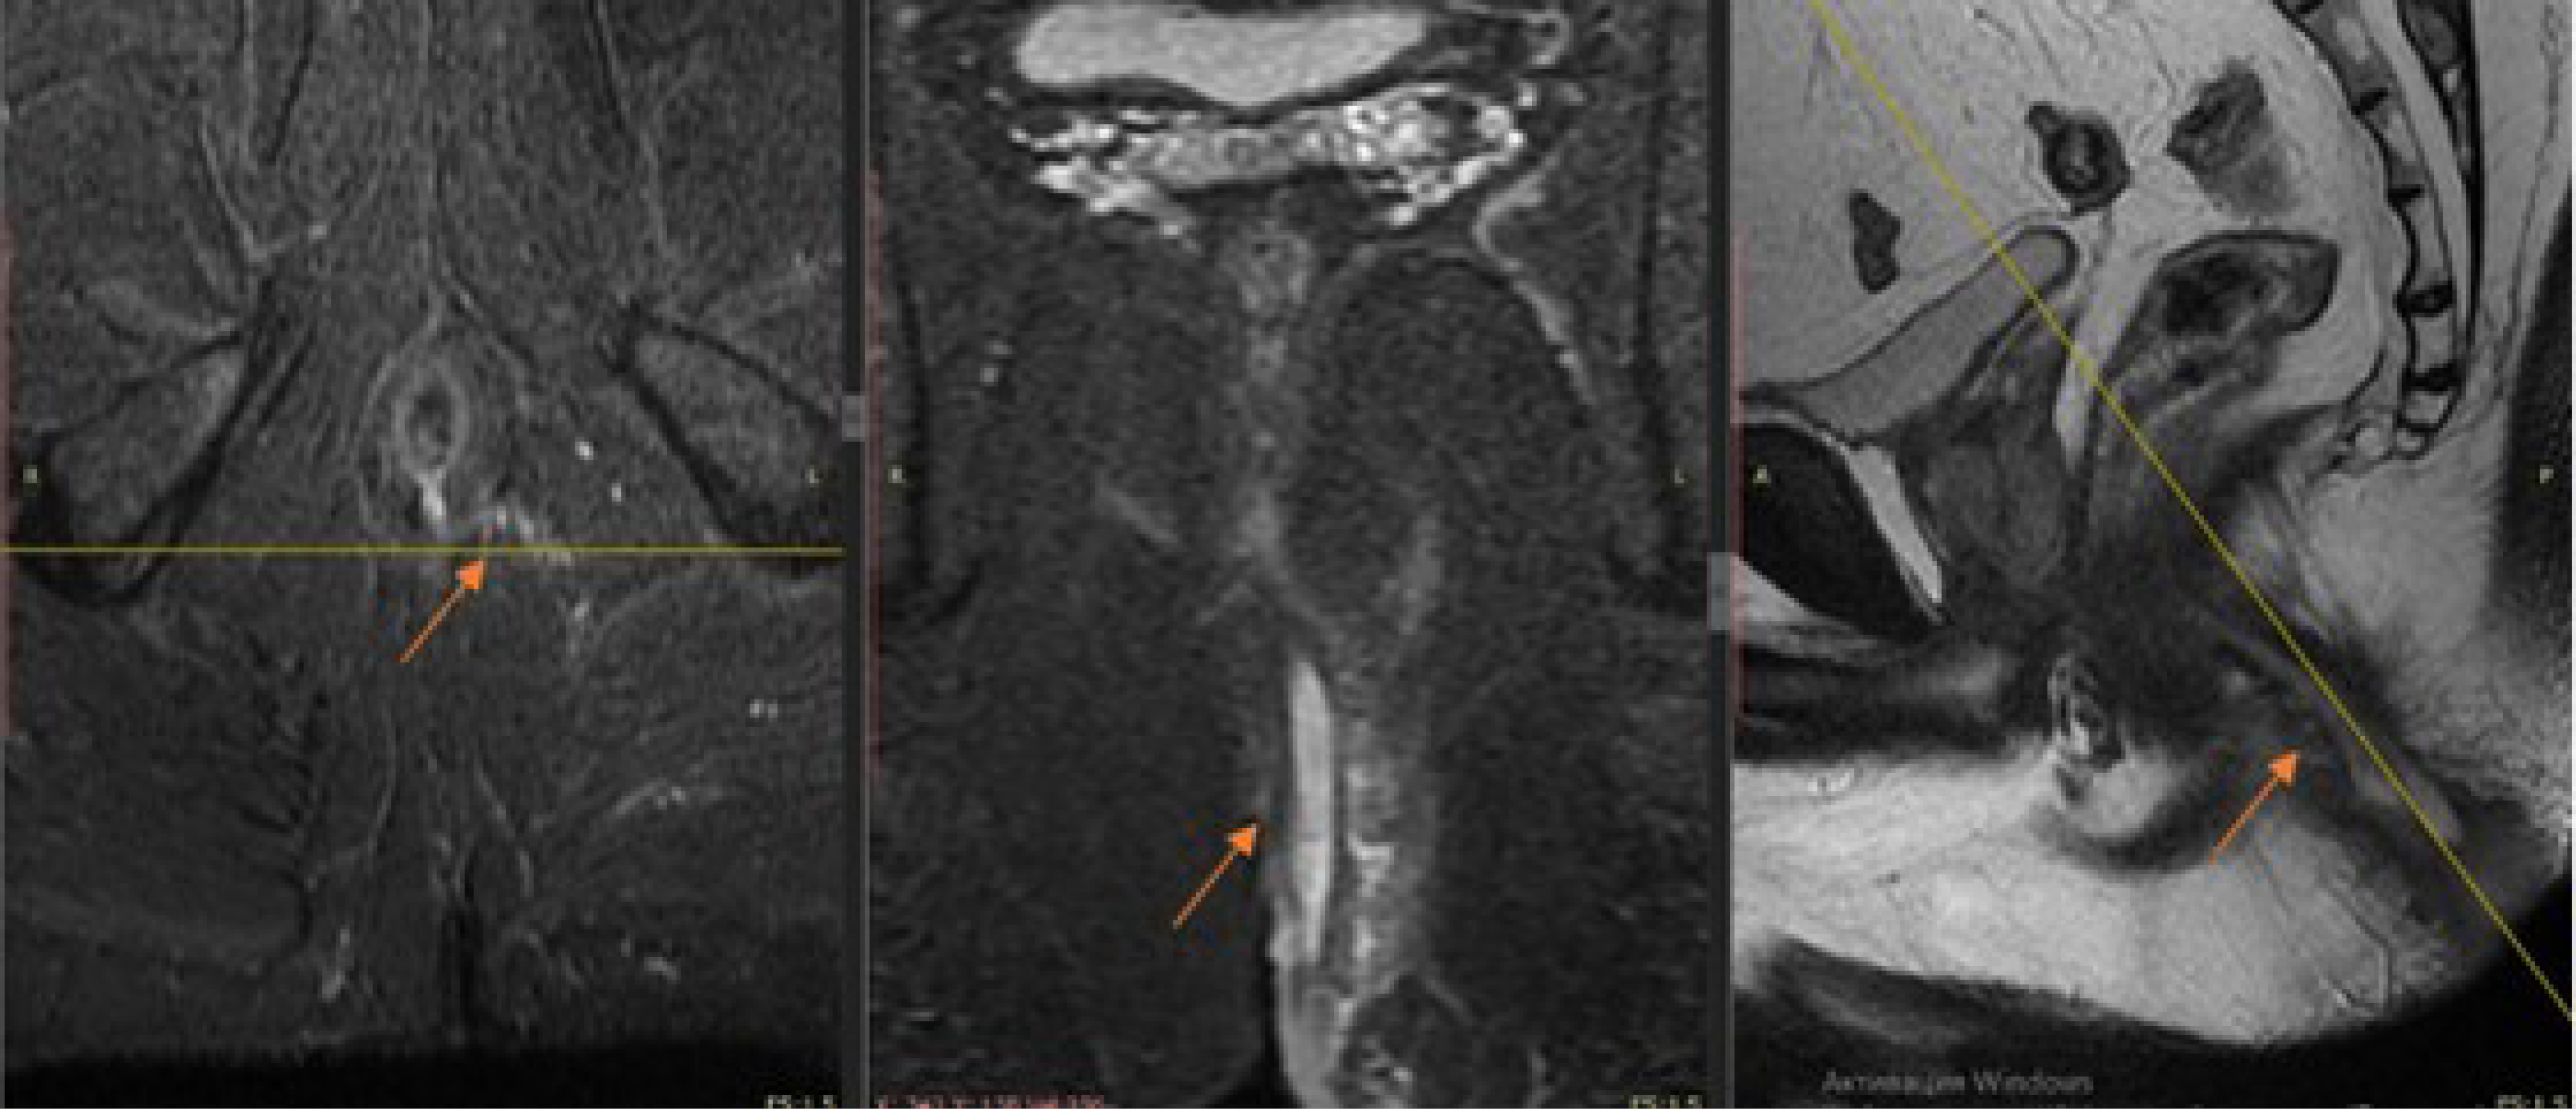

При МРТ исследовании во всех случаях внутреннее свищевое отверстие визуализировалось в виде дефекта слизистой анального канала, от которого начинается свищевой ход. Свищевой ход визуализировался в виде гиперинтенсивного сигнала в T1 FS импульсной последовательности от гнойного содержимого в просвете свищевого хода (рис. 1).

Рис. 1. МРТ пациента А., 36 лет. Транссфинктерный свищ заднего прохода, захватывающий более 30% сфинктера (стрелка).

Fig. 1. MRI of patient A., 36 years old. Complex transsphincter fistula (arrow).

Свищевой ход с указанием внутреннего свищевого отверстия при предоперационной МРТ был визуализирован у всех 76 (86,4%) пациентов. Наличие самого свищевого хода подтверждено у 76 (86,4%) больных.

По данным МРТ транссфинктерный свищ заднего прохода с захватом более 30% сфинктера выявлен -у 61 (69,3%) пациента. Интраоперационно такой тип свища обнаружен - у 63 (71,6%) больных. Экстрасфинктерные свищи по данным магнитно-резонансной томографии выявлены у 15 (17,0%) пациентов и подтверждены при проведении операции – у 13 (14,8%) больных.

Таким образом, при МРТ описании топографии свищевого хода и интраоперационной находке имелись расхождения в 2 (2,3%) случаях - транссфинктерный свищ, захватывающий более 30% сфинктера, был ошибочно принят за экстрасфинктерный свищ. Ошибка в описании, при ретроспективном анализе, могла быть связана с близким расположением свищевого хода и глубокой порцией наружного сфинктера.